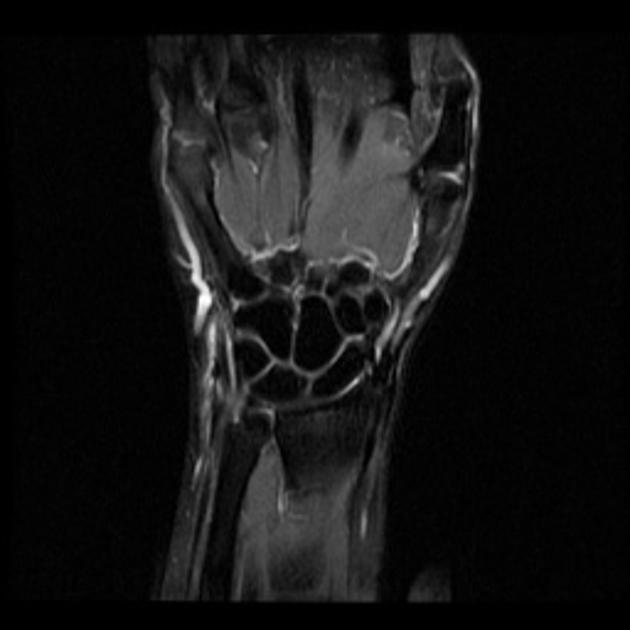

From www.slideshare.net

Anatomy and imaging of wrist joint (MRI AND XRAY) Mri Anatomy Extensor Carpi Ulnaris It is composed of the triangular fibrocartilage disc (tfc), the dorsal and volar radioulnar ligaments, the ulnar collateral. The fifth compartment contains the extensor digiti minimi tendon while the sixth compartment contains the extensor carpi ulnaris tendon. Ultrasound and mri are the mainstays of ecu tendon imaging, with ultrasound offering the advantage of dynamic assessment, doppler interrogation for inflammation,. 1,. Mri Anatomy Extensor Carpi Ulnaris.

From www.kenhub.com

Wrist MRI Interpretation, landmarks, anatomy Kenhub Mri Anatomy Extensor Carpi Ulnaris The fifth compartment contains the extensor digiti minimi tendon while the sixth compartment contains the extensor carpi ulnaris tendon. 1, flexor carpi ulnaris m & t. Ultrasound and mri are the mainstays of ecu tendon imaging, with ultrasound offering the advantage of dynamic assessment, doppler interrogation for inflammation,. The anatomy of ecu results in a relatively. Tendon and its retaining. Mri Anatomy Extensor Carpi Ulnaris.

From www.vrogue.co

Coronal Section Of Tfcc Anatomy Ecu Extensor Carpi Ul vrogue.co Mri Anatomy Extensor Carpi Ulnaris 3, extensor carpi ulnaris t. The fifth compartment contains the extensor digiti minimi tendon while the sixth compartment contains the extensor carpi ulnaris tendon. It is composed of the triangular fibrocartilage disc (tfc), the dorsal and volar radioulnar ligaments, the ulnar collateral. Ultrasound and mri are the mainstays of ecu tendon imaging, with ultrasound offering the advantage of dynamic assessment,.. Mri Anatomy Extensor Carpi Ulnaris.